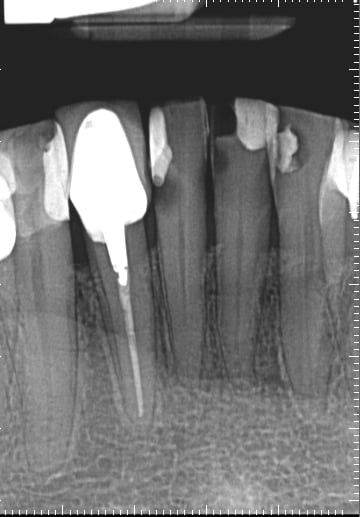

2. What option can describe the post placement in the X ray bellow for the tooth # 4.6?